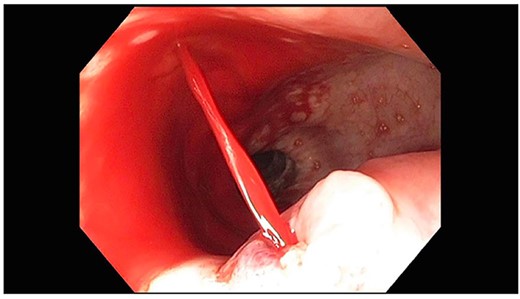

A 71-year-old male with past medical history of type 2 diabetes and hypertension presented to the emergency department at St. Joseph’s University Medical Center with severe respiratory distress. On nonrebreather, the patient’s oxygen saturation was 49%. The patient was subsequently intubated. Evaluation revealed pneumonia secondary to COVID-19 leading patient to be intubated on ventilator support for 4 weeks. During this time patient was maintained on enteral feeding through nasogastric tube, and was on gastrointestinal prophylaxis Protonix 40 mg daily for the duration of his admission. Ultimately, the patient made full recovery and was sent home; however, approximately 3 weeks later, he presented to the emergency department due to syncope. The patient experienced large-volume bright red hematemesis. He became hypotensive and was transfused three units of packed red blood cells and started on pressors. The patient was intubated and transferred to the intensive care unit (ICU) with acute blood loss anemia and hypovolemic shock. Here, an esophagogastroduodenoscopy (EGD) was performed revealing midesophageal bleed (Fig. 1). Hemostasis was achieved with clipping; however, post-procedurally, the patient again became hypotensive. Repeat EGD showed a nonbleeding esophageal ulcer with three clips in good position (Fig. 2). Computed tomography (CT) angiogram of the thorax was performed revealing an actively bleeding aberrant right subclavian artery perforating into the esophagus (Figs 3 and 4). The right subclavian artery was noted to be of normal caliber without ectasia or aneurism and the esophagus was free of any other pathology. Thoracic and vascular surgery were consulted; however, the bleed was deemed of nonsurvivable pathology due to comorbidities and current clinical status. Ultimately, the family of the patient decided to withdraw care and the patient passed.

Repeat EGD showing three clips from prior EGD; no evidence of active bleeding.